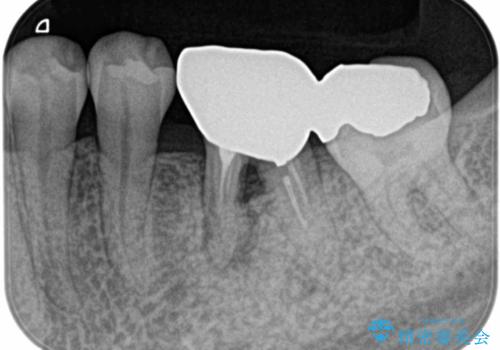

- Ⅲ度の分岐部病変をきたした第1大臼歯を抜去、待時しインプラントによる咬合回復を計画した。

奥歯の根の又の部分の歯周病(=分岐部病変)が進行してしまった場合、

ケースによりますが、いずれの場合も不安要素をかかえたまま歯を温存することになるため、それらを取り除く・かつ感染源を取り除くために歯を抜去するのも効果的な治療法といえます。